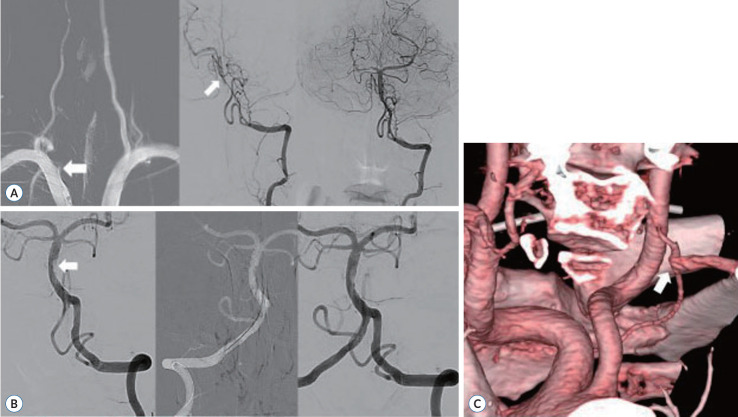

Objective: The dominant vertebral artery (VA) approach is primarily considered in mechanical thrombectomy (MT) for acute occlusion of the vertebrobasilar (VB) artery. As accessing the dominant artery is sometimes difficult, we present our experience treating acute VB stroke via a nondominant VA approach through a comparison with the dominant VA approach.

Conclusion: In MT for VB occlusions, nondominant VA approach may be an option in situations when the vessel is accessible, stable, or less risky, as recanalization can be achieved without rescue balloon angioplasty and/or stenting.